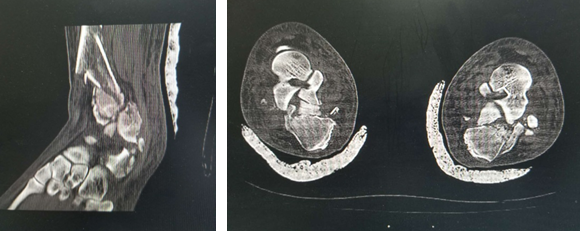

在必威官方首页官网betway,急诊医生给华大姐完善各项检查,发现她的伤情很严重:双pilon骨折,双跟骨骨折,腰椎多发骨折。急诊医生立刻联系足踝科徐明亮主任前来会诊,徐主任仔细检查了华大姐的病情,安排她先进行距骨牵引,消肿一周,等待合适的手术时机。

术前

“病人双侧跟骨粉碎性骨折,胫骨远端粉碎性骨折,受伤暴力大,周围软组织损伤也比较重,短时间内局部出现张力性水泡,早期切开后,一是容易导致伤口难以缝合,另外也增加了感染的机会,所以要在消肿以后,再给她切开复位内固定,减少患者伤口感染的几率。”徐明亮主任说。